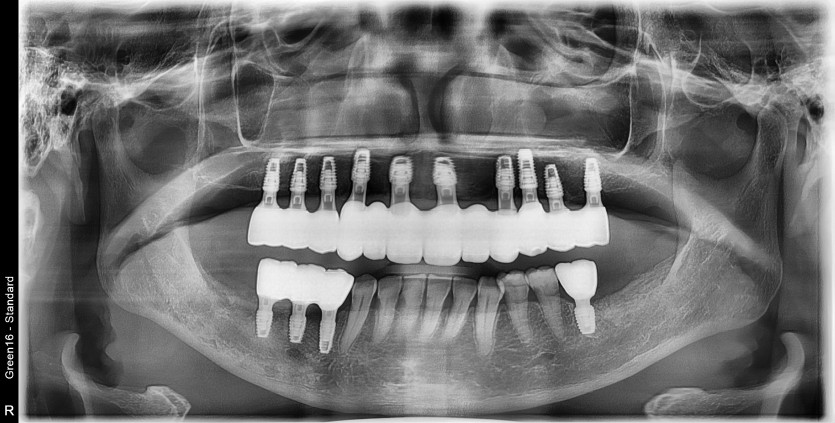

만 52세 상악 전체 임플란트 증례(하악 일부)

상악 전체 임플란트 증례입니다.(하악 일부)

14개의 임플란트로 완성하였습니다.